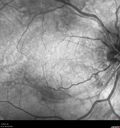

Grade 4 hypertensive retinopathy444 views55 year old man Hhe did have headaches a few weeks ago and also some nausea and vomiting. He noticed for a few weeks the vision in the left eye was blurred and that the vision in the left eye is dark.

VA OD: Dcc20/20

VA OS: Dcc20/100-1

He was admitted directly to ICU for blood pressure control (290 / 170 mmHg)

3 weeks later his VA increased to 20/20 OD, 20/32 OSJan 29, 2019